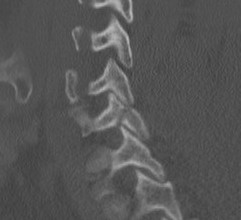

< 40% of the lateral mass

Superior articular facet fracture approximately 50% of the lateral mass